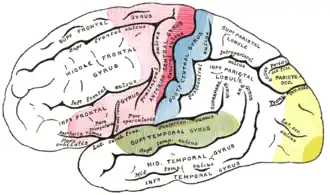

- Mit dem Begriff der zerebralen Syndrome werden zunächst die vier Gruppen hirnlokaler Syndrome zusammengefasst. Es handelt sich dabei um die Hemisphärensyndrome, die Hirnstammsyndrome, die extrapyramidalen Syndrome und die Kleinhirnsyndrome. Diese Syndromgruppen lassen sich noch weiter untergliedern.

Pyramidenbahnzeichen: Die Pyramidenbahn besteht aus einem Bündel von Nervenzellfortsätzen, die von Stirnhirn bis zu den ersten Umschaltstellen im Rückenmark ununterbrochen durchlaufen. Diese Zellen sind so etwas wie ein Schrittmacher der willkürlichen Bewegungen. Der Name Pyramidenbahn stammt von einer Struktur im Hirnstamm (der pyramis), durch die die Pyramidenbahn hindurchläuft. Wenn dieses Nervenbündel an irgendeiner Stelle unterbrochen wird, kommt es zu einem typischen Funktionsausfall: einer spastischen Lähmung (Kraftminderung mit Muskeltonuserhöhung). Die Ursachen können völlig unterschiedlich sein: Eine Verletzung der Wirbelsäule und des Rückenmarkes, eine Durchblutungsstörung im Hirnstamm, eine Hirnblutung im Bereich der sogenannten Kapsel oder ein Tumor in der Großhirnrinde an der entsprechenden Stelle. Neben der Lähmung und der Muskeltonuserhöhung finden sich dann häufig sogenannte Pyramidenbahnzeichen. Man meint damit in erster Linie das Anheben (Dorsalextension) der großen Zehe beim Bestreichen der Fußsohle an ihrem Außenrand (Babinski-Reflex).

Die alte Dame mit dem Hirnstamminfarkt ist ein Musterbeispiel für die so genannte topische Diagnostik in der Neurologie. Die Kombination eines Hornersyndroms mit einer kontralateralen Störung der Temperaturempfindlichkeit deutet immer auf den Hirnstamm und dort in den Bereich der Medulla oblongata. Entscheidend für das Verständnis der Störung ist, dass im Bereich des Hirnstamms einerseits Kerngebiete der Hirnnerven liegen und andererseits Bahnen für Motorik und Sensibilität. Die enge Nachbarschaft dieser Strukturen an dieser Stelle im Gehirn führt zu Störungen in weit entfernten Körperteilen, die von diesen Strukturen versorgt werden.

Syndromale Formulierung im Sinne einer neurologisch topischen Diagnose: Die Lokalisation der gestörten Hirnregion lässt sich weiter eingrenzen, indem der Neurologe den Patienten beide Arme mit geschlossenen Augen vor sich halten lässt: der linke Arm zeigt eine Einwärtsdrehung. Beide Beine sind in der neurologischen Untersuchung unauffällig. Der Neurologe vermutet den Ort der Läsion in der rechten Großhirnhemisphäre in der sogenannten Präzentralregion.

Ätiologische Diagnose: Da der Patient Gefäßrisikofaktoren hat (Alter, Rauchen, Hypertonie) wird eine Durchblutungsstörung im Versorgungsgebiet der Arteria cerebri media rechts vermutet. Diese Vermutung kann durch bildgebende Untersuchungen des Gehirns und vor allem eine Gefäßdarstellung bestätigt oder widerlegt werden.